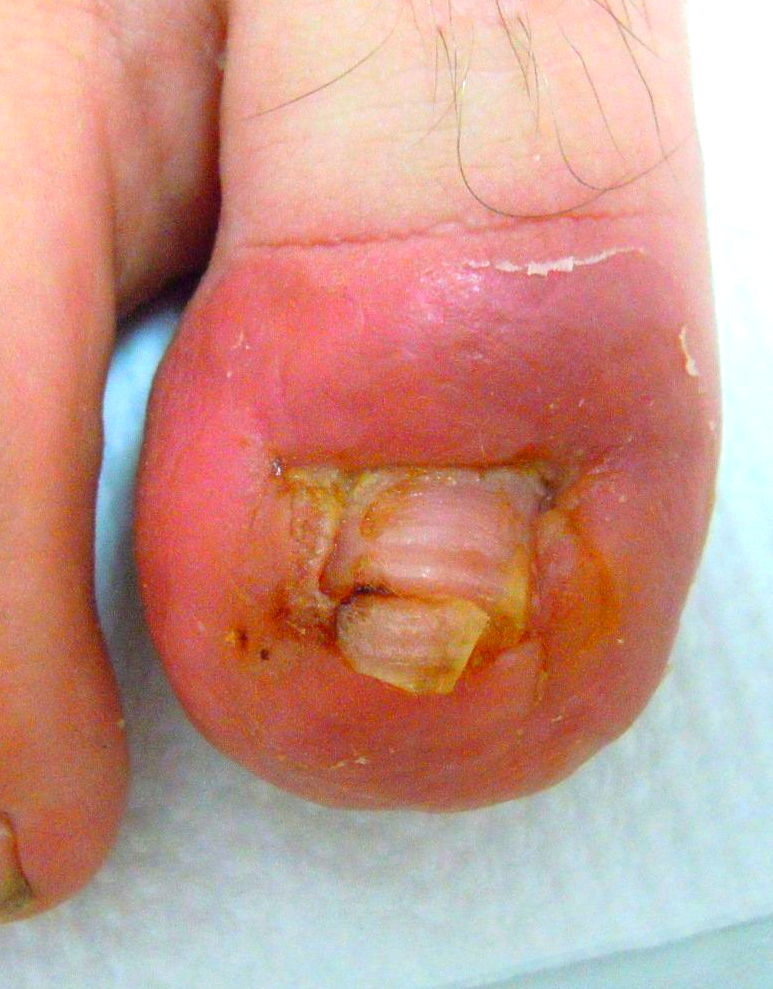

1.) Akutfall am Nagel

👉 Im Folgenden ein Akutfall der besonderen Art:

Kommt nicht sehr oft aber doch immer wieder einmal vor.

🔴 Der Nagelspan kommt bereits DURCH das Weichgewebe.

In Vergrößerung am Monitor auf Bild 2